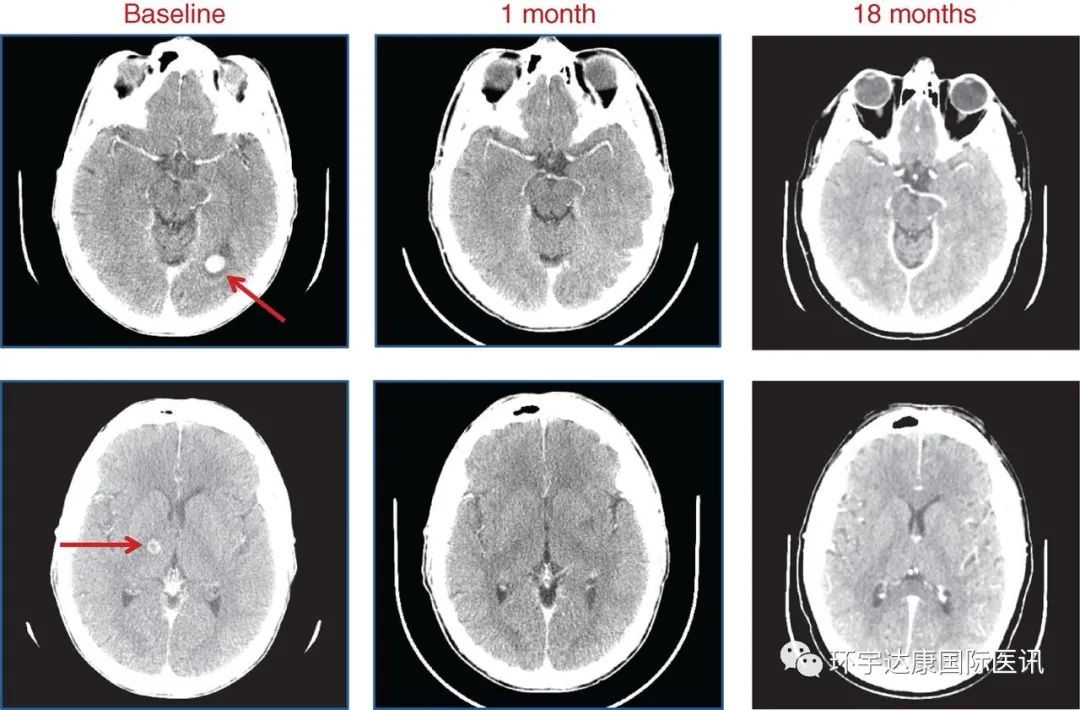

一位存在SQSTM1–NTRK1重排肺癌患者出现了严重的脑转移,有15~20个病灶,下面的CT 显示了左侧枕叶(顶部)和右侧丘脑(底部)的转移(红色箭头)。患者接受了恩曲替尼的治疗,在使用 entrectinib 1 个月和 18 个月时做了CT复查,显示在治疗18个月时,患者的病灶已经全部消失,(数据截止时)评效获得 CR(完全缓解)。